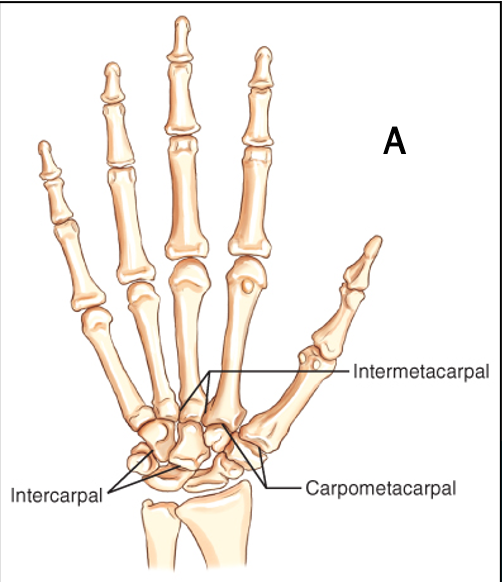

Q

What type of synovial joint is this

A

Plane (gliding)

Carpals shown